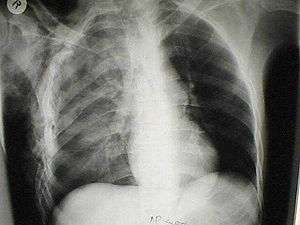

A chest X-ray of a right sided pulmonary contusion associated with flail chest and subcutaneous emphysema

A chest injury is any form of physical injury to the chest including the ribs, heart and lungs. Chest injuries account for 25% of all deaths from traumatic injury.[1] Typically chest injuries are caused by blunt mechanisms such as motor vehicle collisions or penetrating mechanisms such as stabbings.[2]